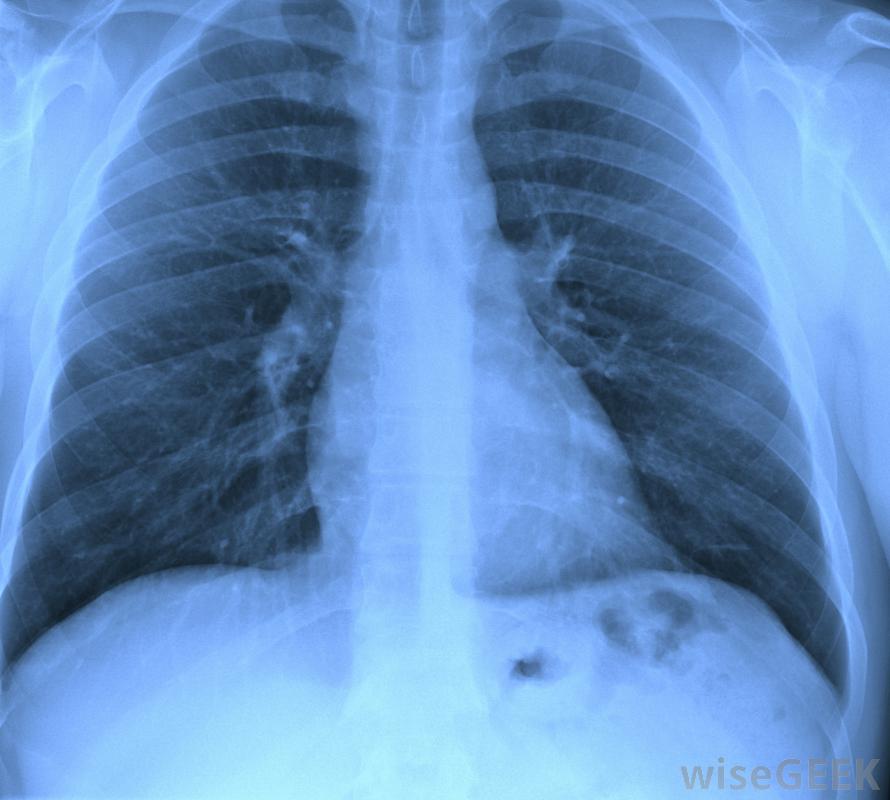

医学专业人员可能会检查胸部X光片,以确定是否有结核病的迹象。随着感染的进展,其他免疫细胞,包括T细胞和B细胞,开始聚集在受感染的巨噬细胞周围。免疫细胞形成团块,称为肉芽肿,是被T淋巴细胞和B淋巴细胞包围的受感染巨噬细胞的小区域。当免疫细胞无法消除感染时,免疫系统会形成肉芽肿,而不是杀死病原体,在肉芽肿中,淋巴细胞分泌细胞因子,帮助杀死入侵的细菌肺结核的典型症状,包括血性痰、咳嗽和发烧,都是由这种慢性感染引起的。感染模式可能包括肉芽肿形成、组织破坏和愈合的多个周期,如果不治疗,可能会持续数年甚至数十年。随着感染的发展,肺组织逐渐变得伤痕累累,降低了受感染者的肺功能。随着疾病的发展,受感染者也变得更具传染性,因为当他们的肺组织变得更坏死时,他们更有可能咳出受感染的物质

肺结核是由一种感染肺部的细菌引起的。通常根据肺结核的症状进行初步诊断肺结核最常见的症状和体征包括慢性咳嗽、痰中带血、盗汗和发烧、胸痛和不明原因的体重减轻有这些症状的人通常会被转诊进行胸部x光片、痰检和其他检查,以确认肺结核的诊断。